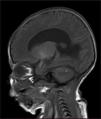

RNM cerebral simple y contrastada. En la secuencia de T1 se evidencia hiperintensidad en la amígdala, además foco hiperintenso yuxtacortical cerebeloso derecho. Ventriculomegalia supratentorial con ascenso y disminución del volumen del cuerpo calloso y medialización de las formaciones hipocampales.

Fue llevado a cirugía al primer día de nacido para corrección de mielomeningocele sin complicaciones. La RNM cerebral y columna vertebral total a los 7 días de vida evidenció en la secuencia de T1 hiperintensidades en el cerebelo, uncus y amígdala bilateral como signos de melanosis, además signos de malformación de Arnold- Chiari tipo II (descenso de las amígdalas cerebelosas a través de la línea de Mc rae de 7,5mm), fosa posterior pequeña asociado a tectum mesencefálico en «pico» y ventriculomegalia supratentorial sin migración transependimaria del líquido cefalorraquídeo (fig. 4).